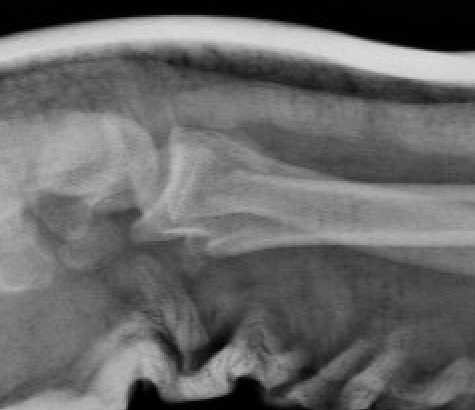

Smith's Fracture

- distal radial fracture with volar displacement

- need long arm cast in supination